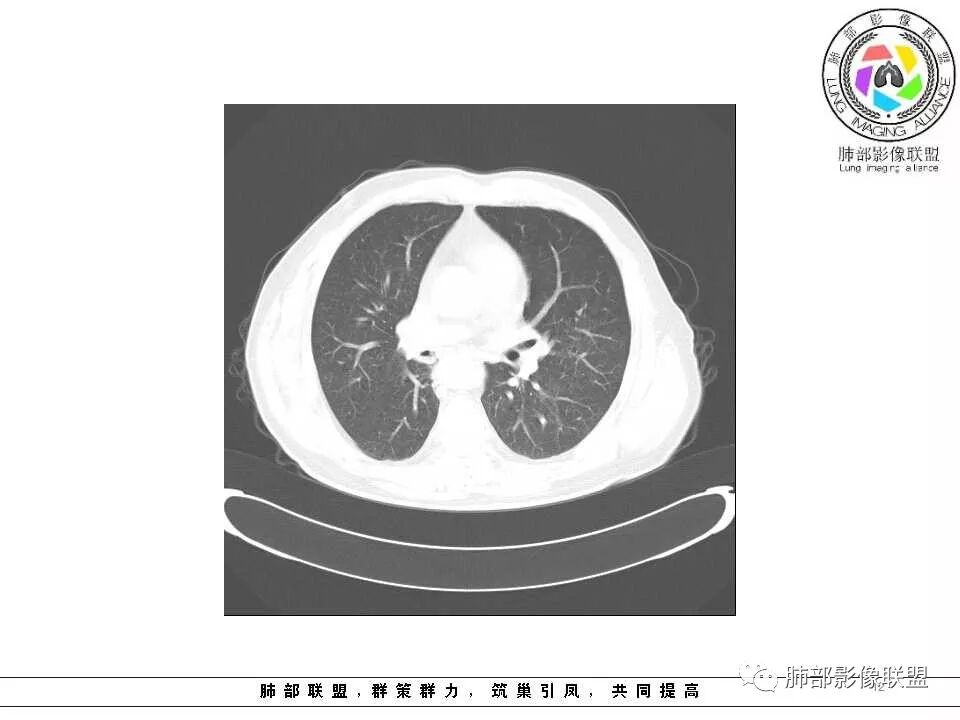

临床特点老年男性、有咯血一个月

影像学特点:肺气肿背景下在大概一年的时间里出现了一个光滑的小结节,因为图像给的不是太薄,与支气管的关系判断不清,从结节周围出现斑片状炎症来判断,应该考虑结节位于支气管内,周围是阻塞性炎症,这样比较容易解释咯血

纵隔窗上似乎结节内可见点状高密度影,同时没有明显肿大淋巴结

所以我考虑支气管内的恶性肿瘤,类癌可能大。

老年男性,左肺舌段见多个小结节灶及斑片状高密度灶、磨玻璃影,结节灶边界清晰,光滑,无明显分叶,密度均匀,周围病灶密度不均,一年内生长,考虑恶性肿瘤并阻塞性肺炎出血,小细胞可能大。

老年男性,肺气肿背景,左肺上叶舌段病灶明显增大,变异膨隆,远端阻塞肺炎,考虑鳞癌。

左肺上叶小结节病灶,形态规则,边缘光滑,密度至密,远处阻塞性肺炎,病灶与支气管关系密切,给图太少不好观察,考虑神经内分泌癌(类癌),其次鳞癌

左肺上叶光滑结节影 似乎与支气管没有关系  ,给的纵隔窗病灶中心似乎点状钙化  病灶旁有更小结节,与上一年片比较 结节增大明显  考虑恶性 类癌可能

老年男性,肺气肿基础。约一年时间出现左肺上叶舌段支气管近端结节影,远端斑片样阴影,边缘模糊。考虑近端恶性占位,远端有阻塞性炎症。

老年男性,两肺可见小叶中央型肺气肿,提示应该有抽烟史。2016年片,右肺门支气管稍模糊,考虑慢性感染,纵膈淋巴结稍大。但2017年左肺上叶新发占位,堵塞支气管,引起局部肺不张伴感染,且纵膈淋巴结较2016年变大,患者同时伴有咯血,考虑恶性。鳞癌?类癌?小细胞?

老年男性,有咳血病史,左肺上叶舌段一年时间出现新发类圆形小结节,感觉在支气管内,部分凸出气管外,没有mpr不好说,远端肺野斑片模糊影,考虑阻塞性炎症,纵隔无明显肿大淋巴结,小细胞代排,按照发展速度,类癌低度恶性,应该发展缓慢,一年病史,代排,首先考虑鳞癌并阻塞性炎症

肺气肿背景,2016年左肺上叶上舌段见微结节,2017年5月左肺结节增大,密度均匀,边缘光滑锐利,与邻近血管关系密切,血管贴壁走行,外侧见尖状突起,下舌段片状影,沿着支气管走行,内有粘液栓,考虑鳞癌,鉴别小细胞肺癌。

肺气肿背景,2016年左肺上叶上舌段见微结节,一年后左肺结节增大,密度均匀,边缘光滑、膨隆,似见小分叶,下舌段片状影,沿着支气管走行,内,老年患者,咯血1月。考虑恶性病变并阻塞性肺炎,鳞癌?注意鉴别结核。

左肺上叶舌段支气管管壁略增厚 间隔一年 管壁增厚明显 向腔外突出形成结节 管腔闭塞 远端片状及斑片影 纵隔淋巴结增大 肺气肿背景 考虑鳞癌伴阻塞性炎症可能

老年男性,咯血1月,肺气肿背景,16年左肺上叶舌段结节,左肺门疑似淋巴结肿大,呈结节感。17年左肺上叶舌段见沿支气管走行分布结节 远端阻塞性肺炎,左肺门淋巴结肿大明显,首先考虑恶性病变,鳞癌?类癌?

前次片2016年4月20相应位置就有小点状病灶,2017-5-15呈结节影改变,边界膨隆,远端阻塞炎性改变,考虑肺癌,鉴别炎性结节!

老年男性,肺气肿背景,左肺上叶舌段一年前小结节后长大,实性,与邻近气管关系密切,远端有少许小片状炎症类小结节状,左肺门淋巴结肿大,首先考虑恶性,鳞癌可能性大,代排小细胞癌。病灶下方斑片状影,考虑炎症。

老年男性,肺气肿背景,对比前片,左肺上叶舌段结节较前进展,周围有斑片状条状密度增高影,左肺门淋巴结肿大,有咯血史抗炎后效果不佳,目测增强强化不好判断,考虑肺癌并阻塞性肺炎可能,鉴别炎症性肺癌,真菌类肺炎,肺脓肿,肺结核,建议完善肿瘤标志物,结核相关检查,病原体检查。

老年男性,咯血一个月,有慢支病史。左肺上叶舌段可见一类圆形结节影,边缘光滑,远端有片条状影,一年前胸ct基本正常。感觉还是考虑肺癌合并阻塞性炎症。鳞癌还是小细胞?

老年男性,咯血1月,肺气肿背景,左肺上叶舌段见沿支气管走行分布结节,呈葫芦样改变,左肺门淋巴结肿大明显,首先考虑恶性病变,小细胞癌可能